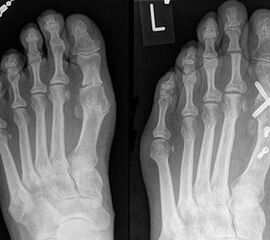

1) Rezidiv bei falschem operativem Verfahren:

Die Röntgenaufnahmen (Abbildung 1) zeigen den Fuß einer 34 jährigen Patientin nach Exostosenabtragung. Der erhöhte intermetatarsale Winkel wurde durch eine alleinige Abtragung der Exostose nicht reduziert. Als weiterer Risikofaktor für ein Rezidiv liegt ein pathologischer Gelenkwinkel vor. Der intermetatarsale Winkel von 18 Grad kann durch eine basisnahe Osteotomie gut korrigiert werden. Da durch die gleichzeitige distale Korrektur des Gelenkflächenwinkels mithilfe einer Reverden-Green Osteotomie ein Längenverlust von ca. 2-4 mm einhergeht, bot sich als proximales Korrekturverfahren die basisnahe Open-wedge Osteotomie an, um bezüglich der Länge des Metatarsale I neutral zu bleiben (Abbildung 2). Die Kombination zweier verkürzender Verfahren (z.B. Lapidus und Reverden-Green) würden zu einem sehr kurzen ersten Strahl führen, mit dem Risiko einer Transfermetatarsalgie. Übersteigt die Verkürzung des Metatarsale I 2 mm, steigt das Risiko für die Entwicklung einer Transfermetatarsalgie deutlich an 8. Die durchgeführte Revision zeigt eine gute Stellung des 1. Strahls bei zentriert stehendem Gelenk.